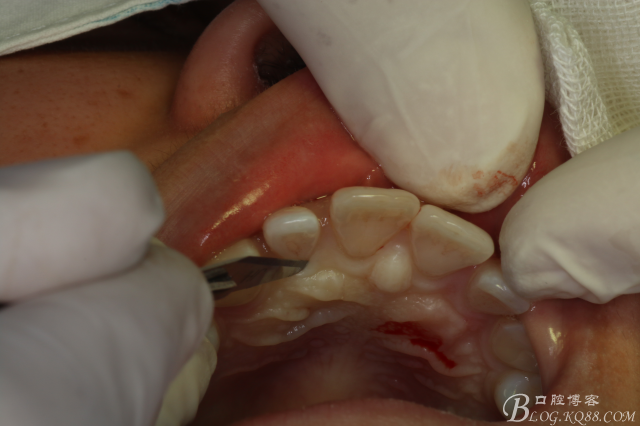

圖7.翻瓣

圖8.翻瓣暴露出鼻腭神經(jīng)管及腭側(cè)骨面